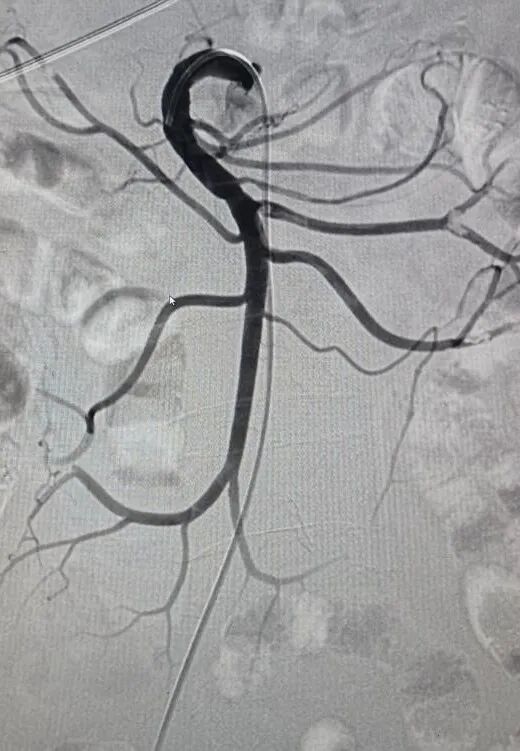

血栓介入治疗:除了常规抗凝治疗,动脉血栓、深静脉血栓开展导管溶栓、机械吸栓术,肺栓塞碎栓术、下腔静脉滤器置入、狭窄静脉支架置入等周围血管疾病的腔内治疗。

▲肠系膜上动脉栓塞吸栓术前后对比